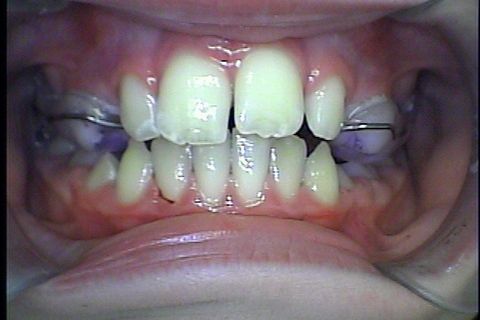

Pós disjunção

Pós Disjunçao

Antes da colocaçao de aparelho fixo